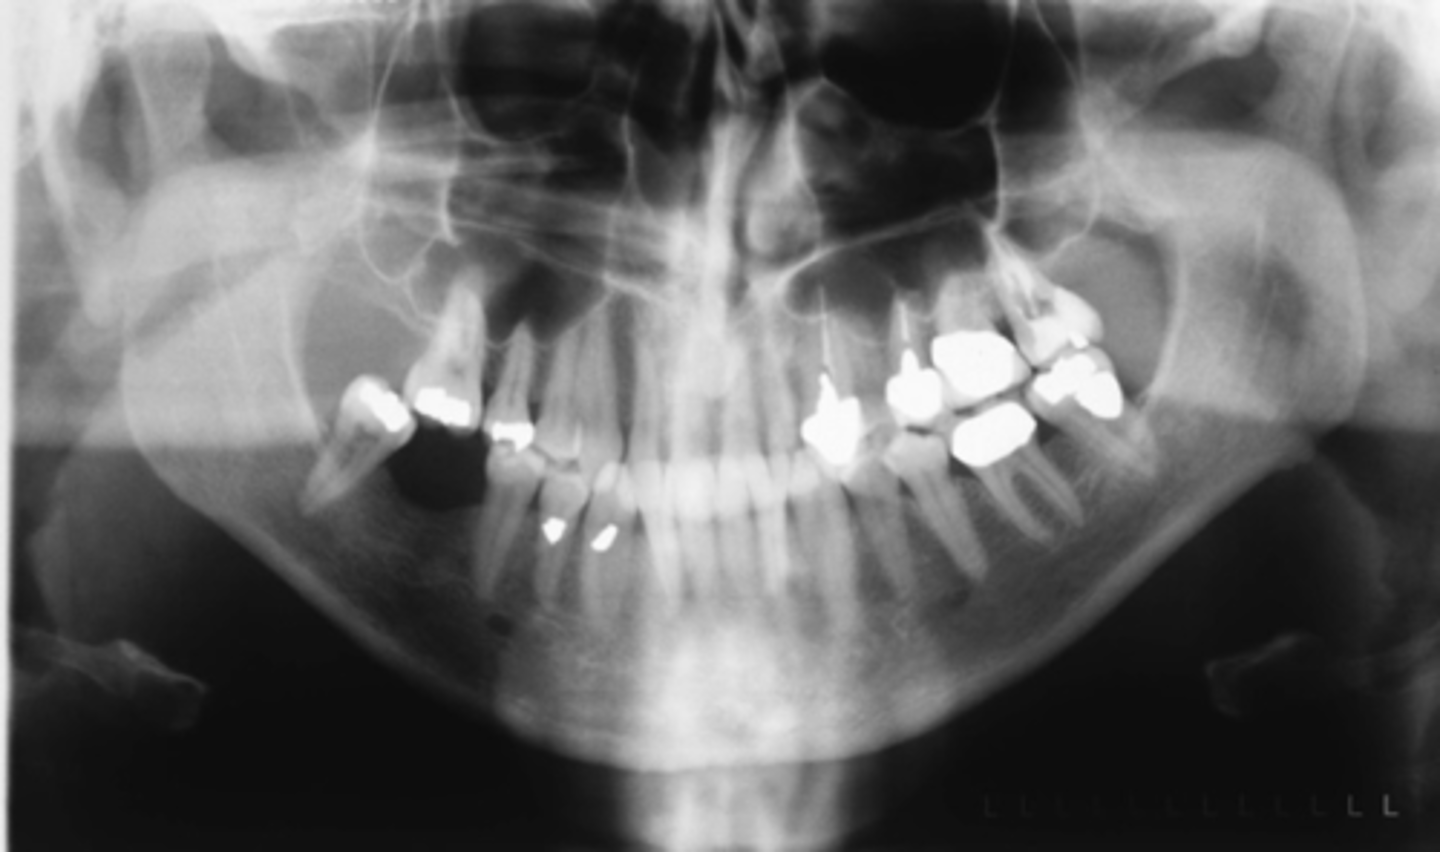

ID the positional error from the radiograph:

right rotation (pts right side is larger)

(And too far back)